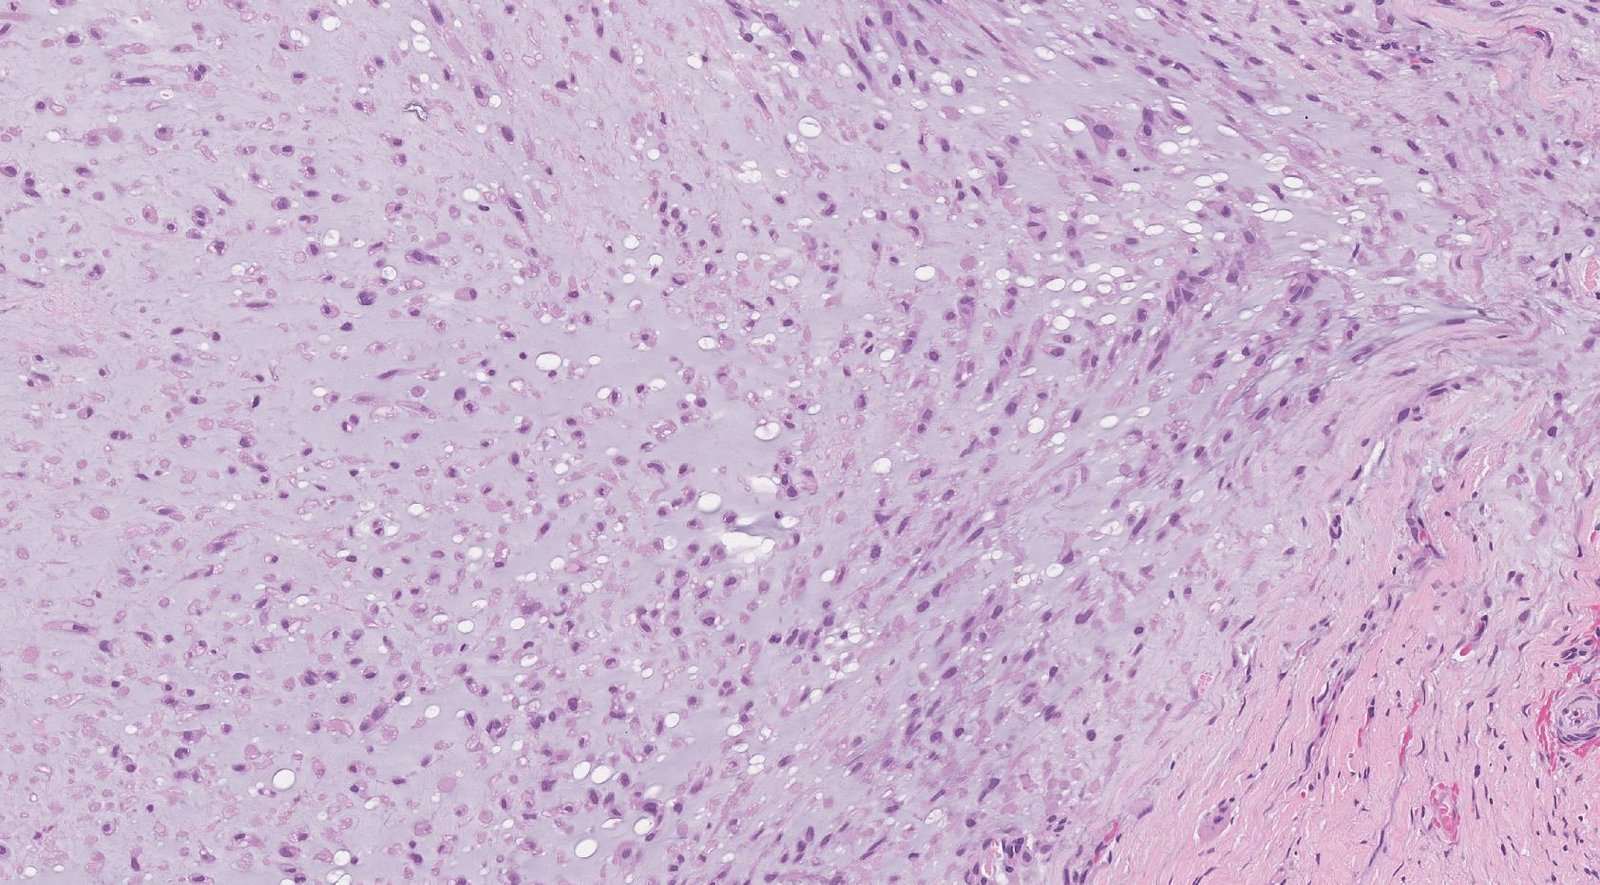

Case: ThighMass4

Final Diagnosis: